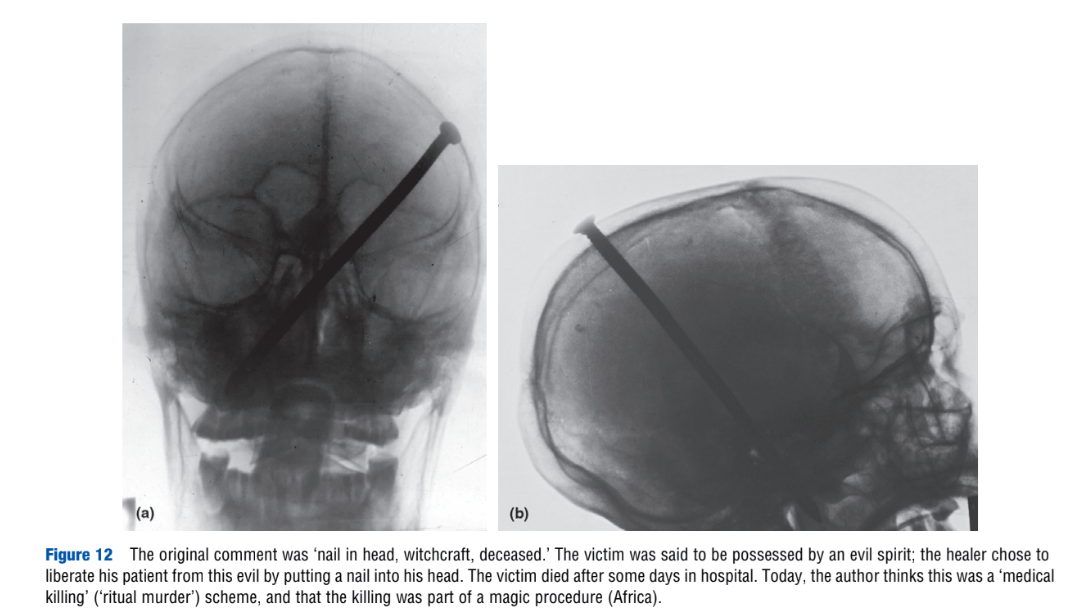

“Torture,” by H. Vogel. Encyclopedia of Forensic Sciences, second edition. 2013.